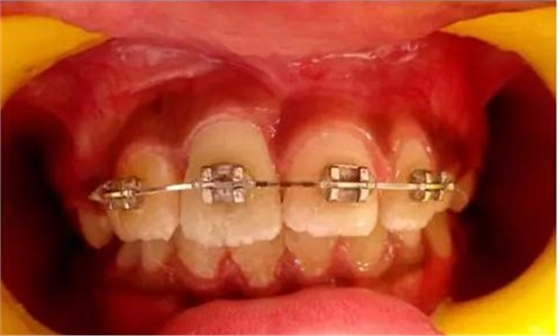

健康的 7 歲男童,前一天摔倒,上頜右中切牙和右側(cè)切牙發(fā)生挫入脫位(圖 1)。無牙外傷史,無神經(jīng)并發(fā)癥病史。檢查發(fā)現(xiàn)雙側(cè)下頜下腺增大。

口腔內(nèi)發(fā)現(xiàn):混合牙列早期,覆蓋正常,安氏I類磨牙關(guān)系。牙11和12齦緣紅腫。

牙11,12 和21對叩診敏感。牙11嚴(yán)重挫入(牙11和牙12的切緣相差7毫米),并挫入牙槽窩。與牙21相比,牙12大約挫入4毫米。